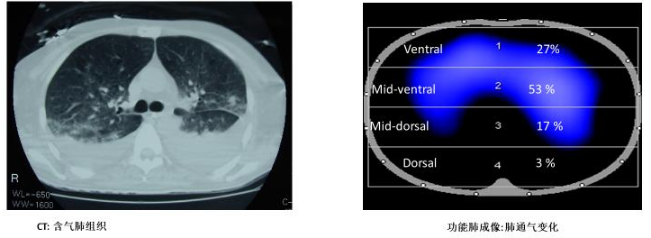

(1)CT法:目前认为CT法是判断肺可复张性的金标准。根据CT值将通气分为四大类:过度通气(<-900 HU)、正常通气(-900~-500 HU)、通气不良(-500~-100 HU)和不通气(>-100 HU)。根据CT值计算复张后获得通气的肺组织重量,复张的肺组织大于9%的重量具有可复张性,此时进行肺复张的效果较好,能够使患者的氧合得到明显改善。其局限性在于耗时较长,需要转运患者,而且具有辐射性,对于危重患者使用受到一定限制,仅作为研究。

下图所示为患者肺内通气情况,不同颜色代表不同的通气状态,绿色为不通气区域,蓝色为通气减低区,紫色为正常通气区,橙色为过度通气区。

图片